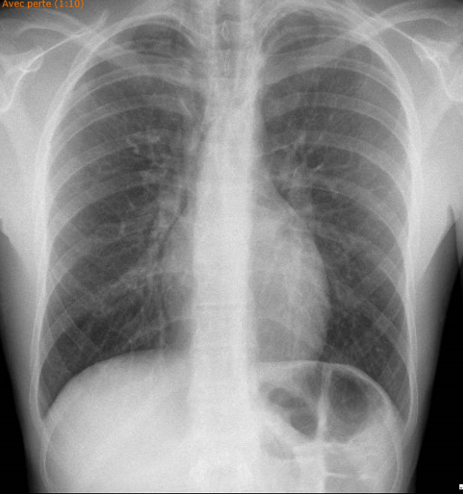

Voici sa radiographie du thorax :

Quel est ton diagnostic ?